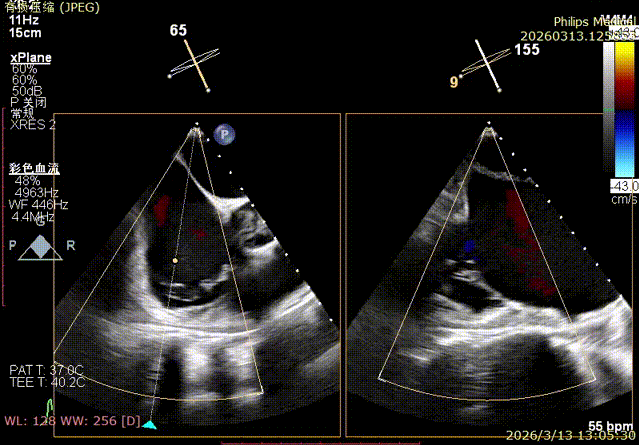

Preoperative echocardiographic evaluation: Severe tricuspid regurgitation (4+, average vena contracta 12 mm), with the regurgitant orifice located at the anteroseptal and central regions. Mild dilatation of the tricuspid annulus (average annulus diameter 41.8 mm).

Transesophageal echocardiography upon admission showed regurgitant jets at the anteroseptal and central regions.

Baseline preoperative regurgitation